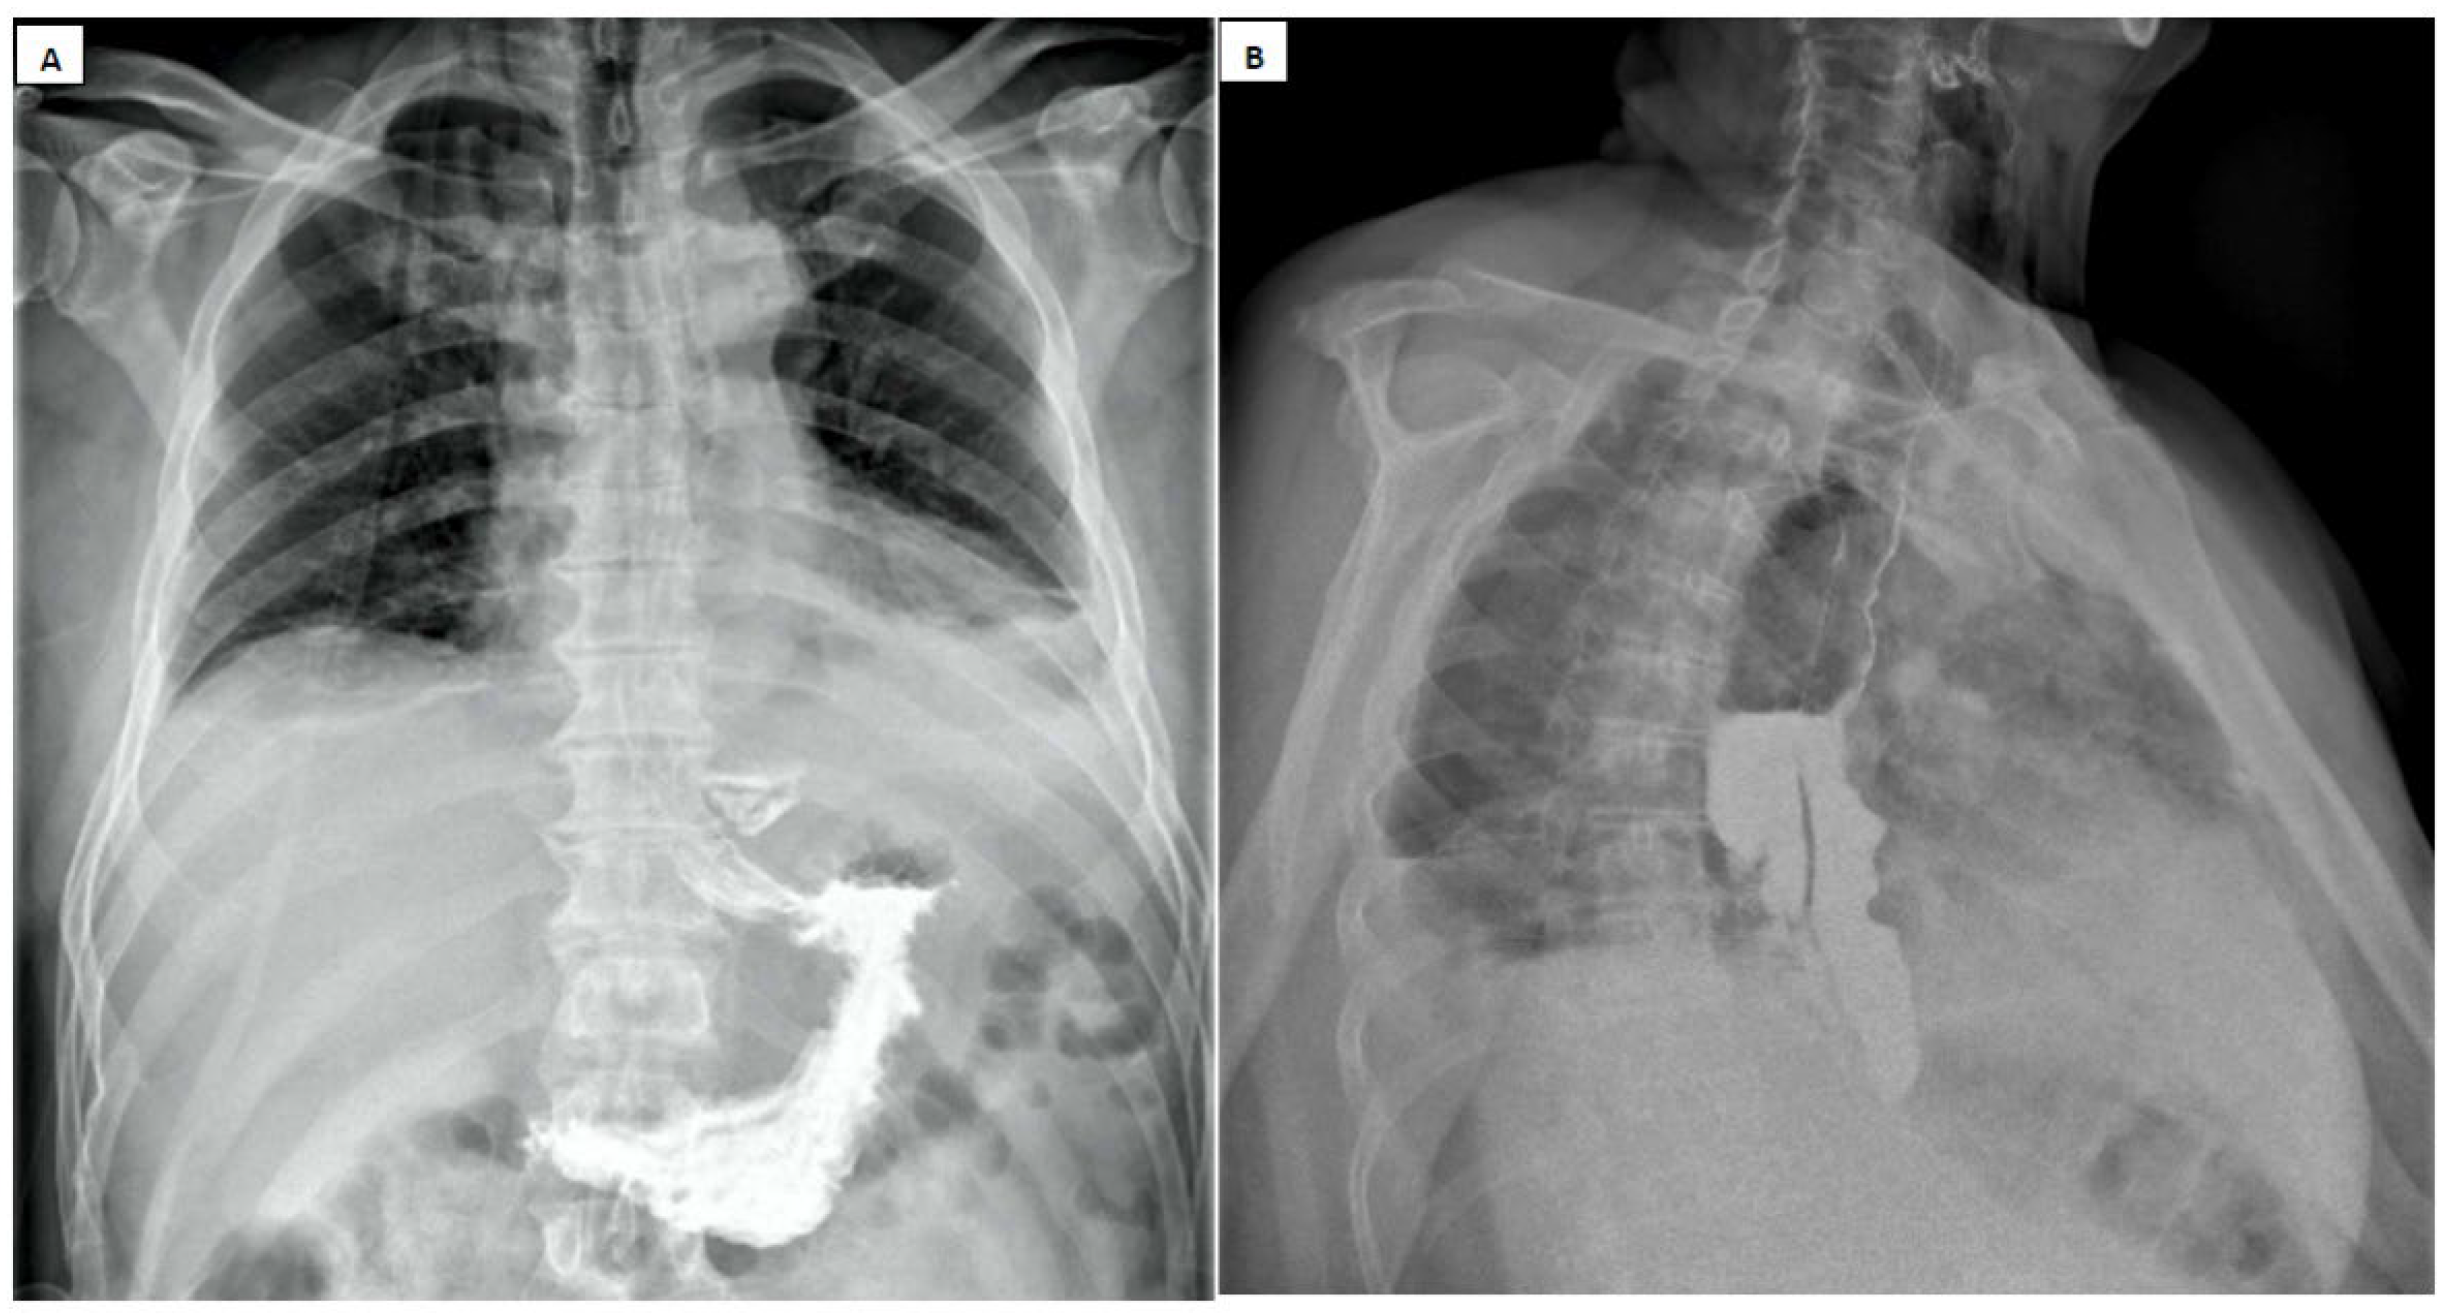

8. Paraclinical Investigations

- Pneumomediastinum

- Pneumothorax (especially left-sided)

- Pleural effusion (especially left-sided)

- Localized periaortic gas

- Mediastinal fluid collections

- Thickened esophageal wall

- Gas within thoracic soft tissues, neck, or around major vessels

- Gas in the epidural space

- Pneumoperitoneum

- Gas in the retroperitoneal space

- Oral contrast extravasation from the esophageal lumen [10].